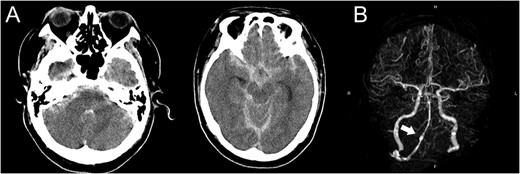

A 48-year-old man was admitted to our hospital because of loss of consciousness after a sudden nuchal pain. Brain computed tomography (CT) showed diffuse SAH (Fig. 1A). The following CT angiogram showed a fusiform aneurysm at the right vertebral artery with contralateral hypoplasia (Fig. 1B). The endovascular procedure was performed under general anesthesia. The patient received a loading dose of 200 mg of aspirin and 300 mg of clopidogrel via a nasogastric tube. A preoperative angiogram showed VAD with a blister at the pseudolumen (Fig. 2A). Initially, a stent (Enterprise, 4.5 mm × 37 mm; Codman, Raynham, MA, USA) was deployed from the basilar artery to the right vertebral artery. A second stent (Enterprise2, 4.0 mm × 30 mm) then overlapped the first stent, covering the pseudolumen (Fig. 2B). Coiling was performed from a microcatheter (Excelsior SL-10/45; Boston Scientific, Fremont, CA, USA), which was jailed in the pseudolumen. After the first coil perforated the blister, a balloon catheter (Scepter C, 4.0 mm × 15 mm; Microvention, Tustin, CA, USA), which was exchanged with a stent delivery catheter, was inflated in the stent. All five small platinum coils (Target nano, 2 mm × 4 cm and 1.5 mm × 2 cm; Stryker, Fremont, CA, USA) completely occluded the pseudolumen (Fig. 2C), and the right vertebral artery was preserved (Fig. 2D). Magnetic resonance imaging, which was obtained 3 weeks after the procedure, showed right cerebellar infarction without damage of the brainstem (Fig. 3). The patient recovered and returned to his former job after 2 weeks of intensive care and 3 months of rehabilitation therapy. An angiogram, which was obtained 6 months after procedure, showed no recurrence of VAD (Fig. 4).

Magnetic resonance images obtained 3 weeks after the procedure shows right cerebellar infarction without damage of the brainstem.